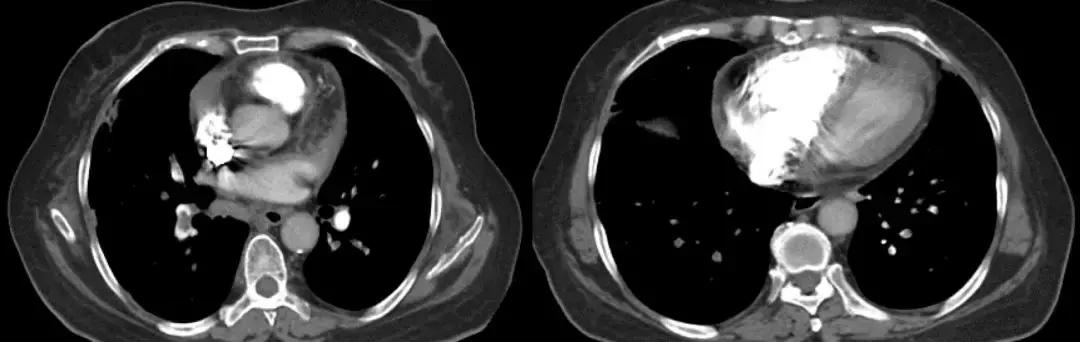

同年11月14日就诊于北京某三甲医院,查血常规:WBC 19.01×10^9/L ,N% 76.6%,ESR 25mm/h,PCT 2ng/ml。 血气分析(未吸氧):PH 7.514、PCO2 24.6mmHg、PO253.2mmHg、HCO3- 19.7mmol/L、BE -1.3mmol/L。 查胸部CT示:右肺上叶、中下叶、左肺下叶胸膜下片状实变影,可疑气管憩室。

肿瘤标记物:CA125 178.60U/ml、NSE 66ng/ml。风湿免疫:抗Ro-52抗体 弱阳性。PCT、ESR、G试验、GM试验正常。CRP :57.00mg/L。TB-SPOT:3.086 IU/ml。血气分析(2.5L/min):PH 7.48、 PCO2 31mmHg、PO2 73mmHg、HCO3- 25.3mmol/L、BE 0.5mmol/L、SO2 96%。 心梗四项:CK-MB 2.10ng/ml,Myo 39.74ng/ml;cTnI 0.017ng/ml;NT-proBNP 4599pg/ml。

经验教训

靠近胸膜下楔形实变影,其底部宽基底于胸膜面,尖部指向肺门,呈驼峰征,提示栓塞动脉供血远端的肺实质出现肺梗死,约可见于30%的肺栓塞患者。长时间抗生素应用无效合并低氧血症的患者一定警惕肺栓塞。